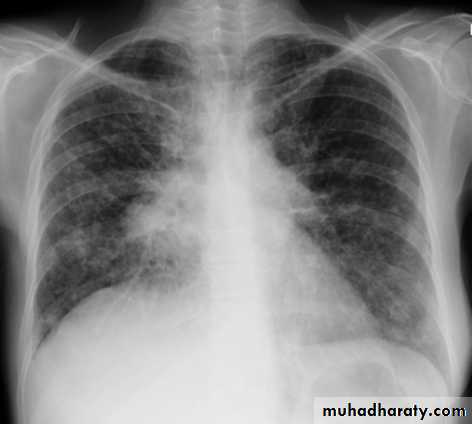

Pulmonary arterial hypertension results from elevation of the resistance in the pulmonary arterial bed, usually at the arteriolar level. It is characterized radiographically by enlargement of the pulmonary trunk and right and left main pulmonary arteries with disproportionately small peripheral vessels This has been referred to as "pruning" of the pulmonary arteries

So the Plain radiograph

elevated cardiac apex due to right ventricular hypertrophy

enlarged right atrium

prominent pulmonary outflow tract

enlarged pulmonary arteries

pruning of peripheral pulmonary vessels